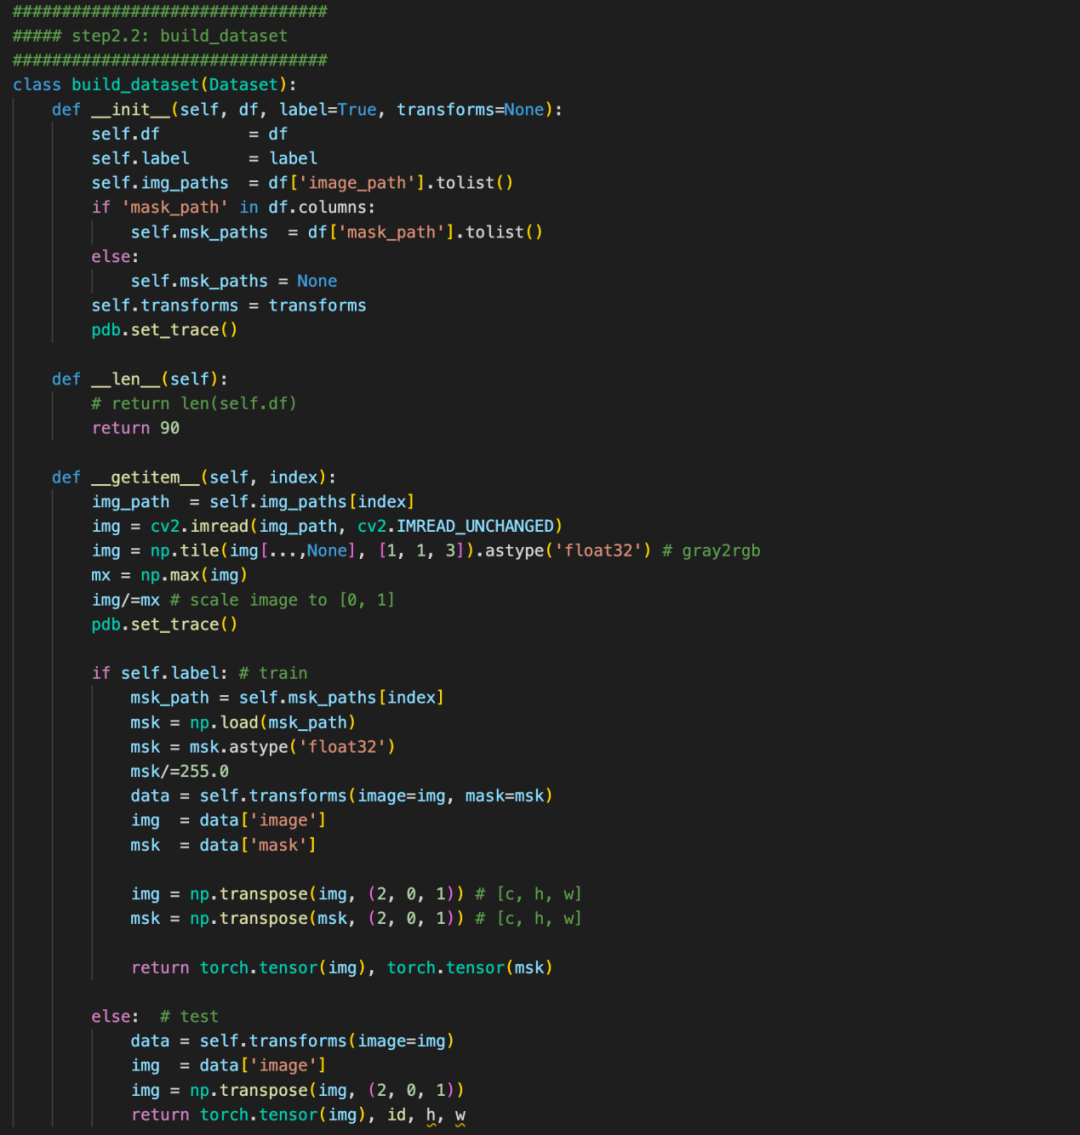

4、baseline

本次提供的baseline分为hypre-parameter, data, model, Loss, train五个方面。

整套baseline的代码非常清晰, 非常适合入门以及后续代码复用。